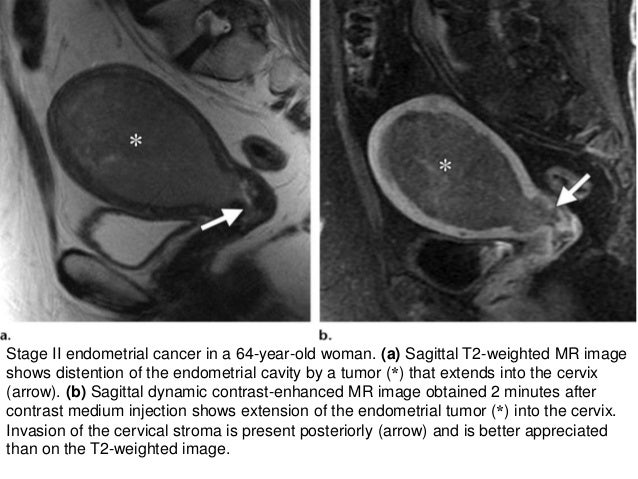

Stage Ii Endometrial Cancer In A 64 Year Old Woman A Sagittal Download Scientific Diagram